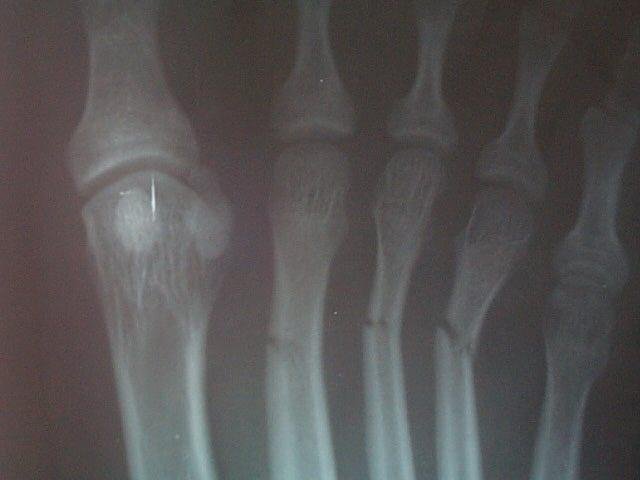

A stress fracture of the metatarsals

is known as a March fracture, because it was first described as a condition

amongst army recruits, marching with heavy loads. The condition usually arises

as a result of unaccustomed loading of the bone, eg a sudden increase in

exercise intensity. It is particularly common in adolescents, and middle-aged

runners.

The 2nd or 3rd metatarsals are the most susceptible to this injury, which

results in pain in the forefoot, aggravated by impact. The onset is sudden

(unlike metatarsalgia, which usually builds up gradually), and the foot will be

swollen over the fracture site. It is very often more painful on the dorsum

(top) of the foot.